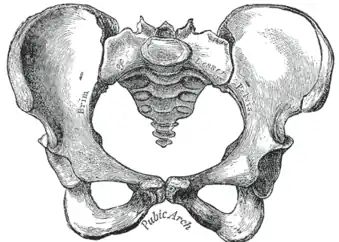

-

Becken -

Das Becken (lateinisch Pelvis) ist bei Landwirbeltieren der Körperabschnitt unterhalb des Bauchs und oberhalb der Beine, bei vierfüßigen Säugetieren der Teil zwischen Bauch und Schwanz. Man unterscheidet beim Menschen zwischen einem großen und einem kleinen Becken (Pelvis major und Pelvis minor). Das große Becken liegt zwischen beiden Darmbeinschaufeln oberhalb der Beckeneingangslinie (Linea terminalis) und gehört eigentlich zum Bauchraum.

Zugleich wird unter dem Begriff „Becken“ auch der knöcherne Teil dieses Körperabschnitts verstanden. Das knöcherne Becken besteht aus den beiden Hüftbeinen (Ossa coxae) und dem Kreuzbein (Os sacrum), sie bilden den Beckengürtel oder auch Beckenring (Cingulum membri pelvini). Bei Säugetieren (einschließlich des Menschen) ist das knöcherne Becken mit der Wirbelsäule über das Iliosakralgelenk gelenkig, aber wenig beweglich[1], verbunden. Durch seine Festigkeit und Stabilität gibt der Beckengürtel dem menschlichen Körper einen sicheren Stand und eine aufrechte Haltung. Zudem umgibt es die Beckenhöhle. Bei Tieren sorgt es dafür, dass die Hintergliedmaßen stabil am Rumpf verankert werden und der von ihnen produzierte Vorschub effektiv auf den Körper übertragen wird. Bei Krokodilen unterstützt der Beckengürtel die Lungenventilation.[2]